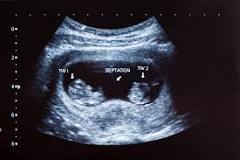

Can twins be detected at 6 weeks?

"You can guess as much as you want, but until you have the ultrasound examination, it's all just speculation," says Dr. Grunebaum. Luckily, most mamas don't have to wait long to know for sure. "Today, twins can usually be diagnosed as early as six to seven weeks of the pregnancy," he adds.